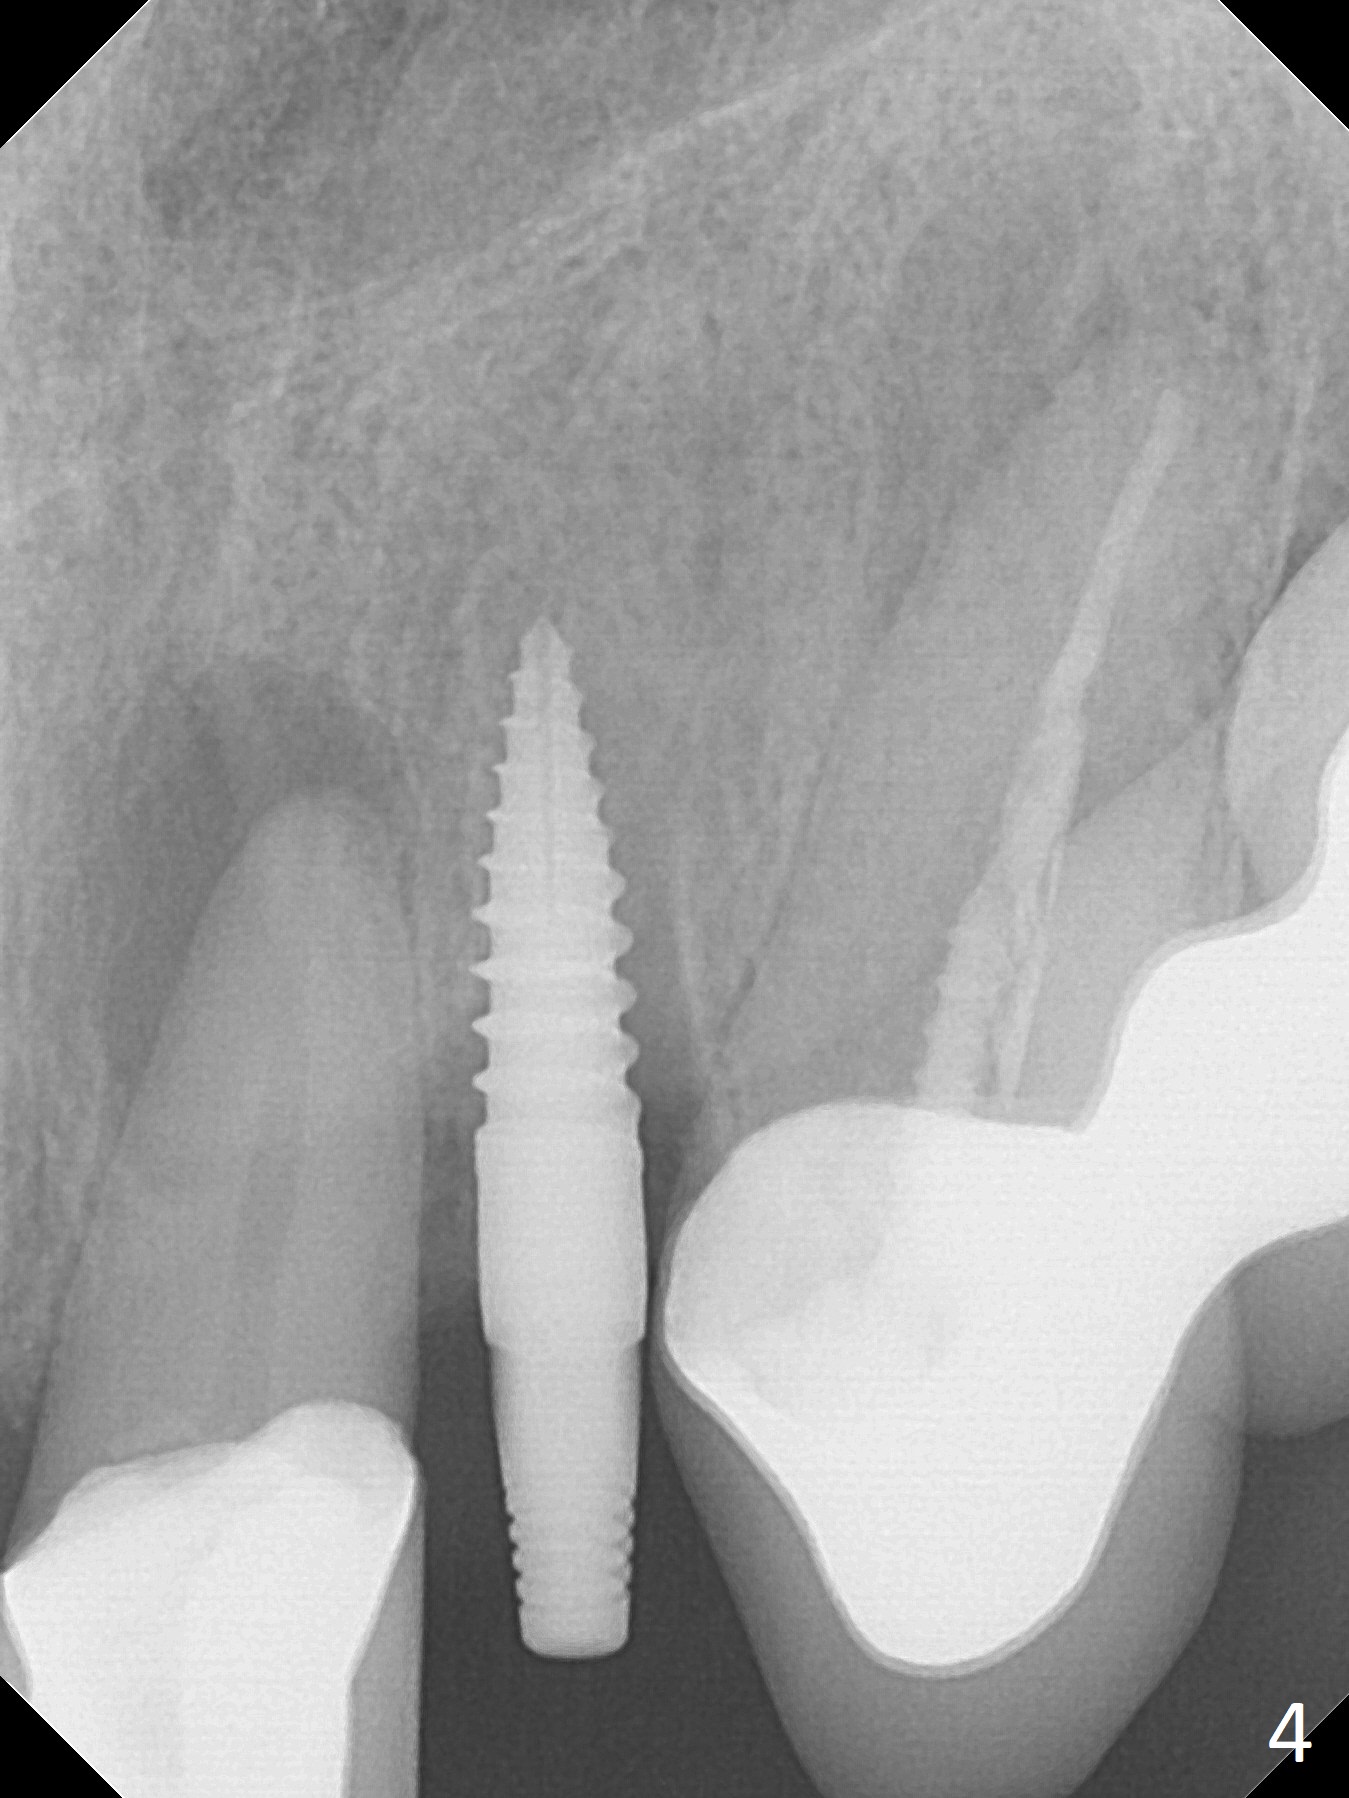

The tooth #10 fractures at the cervix, but is attached to the gingiva.  After extraction of the coronal portion of the tooth, the mesiodistal space palatally is found to be narrow (~4.7 mm, Fig.1).  It appears that a 1-piece implant is indicated because of the narrow mesiodistal space.  In fact the buccal plate of the socket is intact (Fig.2).  The initial osteotomy seems to be mesial (Fig.1) and is moved distal using Lindamann bur.  After sequential osteotomy, a 3x10 mm dummy implant is still mesial (Fig.4).  Following further distalization, a 3x14 mm implant is placed (Fig.5,6; <30 Ncm).  Vera Graft is placed in the remaining socket prior to provisional fabrication (Fig.6 *).  The socket outline disappears 7 months postop (Fig.7).  Panoramic X-ray is taken 1 year 3 month post cementation.